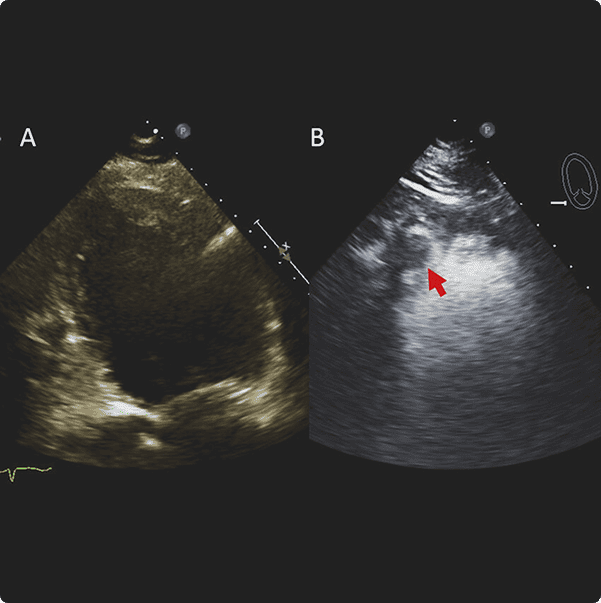

Contrast Transthoracic Echocardiogram (cTTE): Enhancing Heart Imaging Precision

A Contrast Transthoracic Echocardiogram (cTTE) is an advanced cardiac imaging test that employs ultrasound and a contrast agent to obtain clearer and more detailed images of the heart. This diagnostic procedure enhances our ability to visualize and assess specific cardiac structures, providing valuable information for a comprehensive evaluation of your heart health.

How It Works:

During a cTTE, a contrast agent is introduced into the bloodstream through a vein, typically in the arm. This contrast material enhances the visibility of the heart chambers, allowing for a more precise and detailed examination.

Ultrasound: The ultrasound transducer is then placed on the chest to capture real-time images of the heart with enhanced clarity.